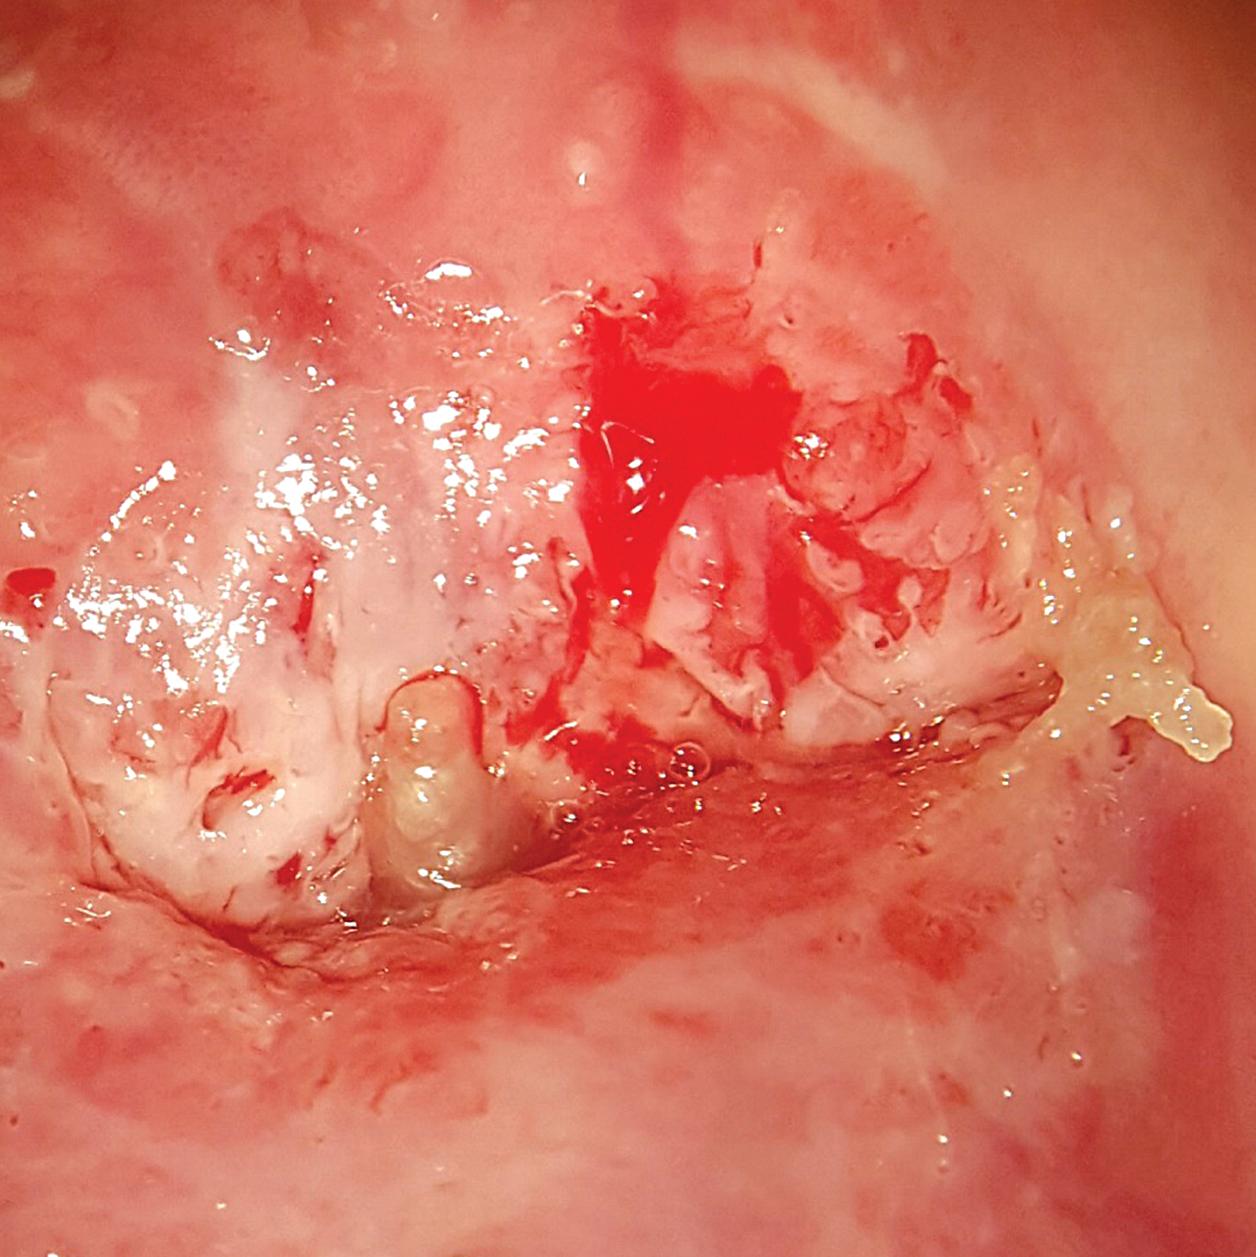

O diagnóstico correto da ectopia é feito por meio do exame colposcópico após a aplicação do ácido acético que tornará a junção escamocolunar mais evidenciada pela presença de um bordelete esbranquiçado. Muitas vezes o fenômeno ectópico é erroneamente diagnosticado levando a tratamentos desnecessários (Figs. 2-18 e 2-19).

que deverá ser aplicado profundamente na vagina em noites alternadas no total de 15 aplicações. O creme vaginal de clostebol também poderá ser utilizado da mesma maneira. Se a queixa permanecer e não ocorrer a epidermização da área, poderá ser realizado ambulatorialmente a aplicação de ATA a 80% sobre a área da ectopia. A aplicação deverá ser antecedida pela colocação de um chumaço de algodão no fundo vaginal que funcionará como protetor, pois o ácido em contato com a mucosa vaginal poderá causar ulcerações na mesma. O cotonete deverá ser pressionado levemente contra o colo até o aparecimento de uma coloração branca no local. As aplicações do produto deverão ser realizadas semanalmente durante em média 3 semanas. Em caso do aparecimento de efeitos colaterais como candidíase vaginal, as aplicações poderão ser feitas quinzenalmente (Fig. 2-20).